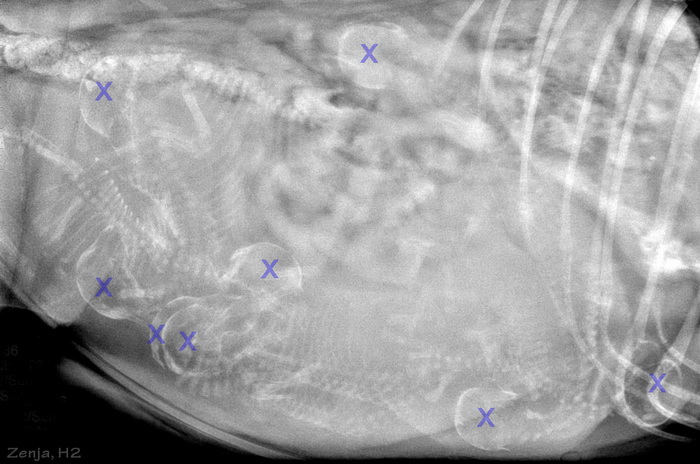

Zenja zur Lewitzperle HD-A1, CEA/PRA/Kat./Dist./MPP-frei, MDR1(+/+) DM N/N, IPD N/IPD, CEA genetisch Carrier |

Entwicklung der einzelnen Welpen: Hardy

Harvey

Hayo

Hilco

Happy Lennja

Hevi

Hilda

allgemeine Bilder des